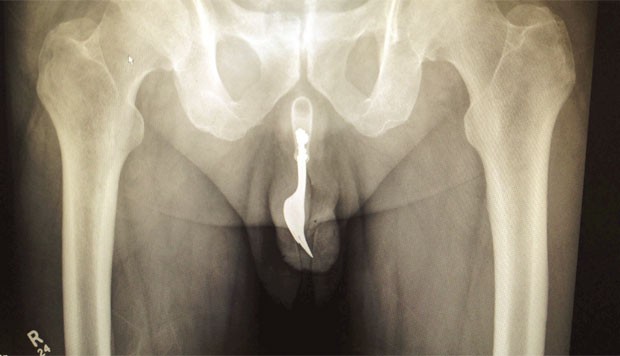

Foto: Reprodução/International Journal of Surgery Case Reports

Um senhor de 70 anos de idade enfiou um garfo de cerca de 10 centímetros pela uretra e teve que ser levado ao hospital de Canberra, na Austrália, e teve que passar por uma cirurgia.

Segundo a edição online do jornal “International Journal of Surgery Case Reports", o homem realizou o ato bizarro com o fim de obter prazer sexual. Ao apalpar a área, os médicos localizaram o talher, que aparentemente estava invisível.